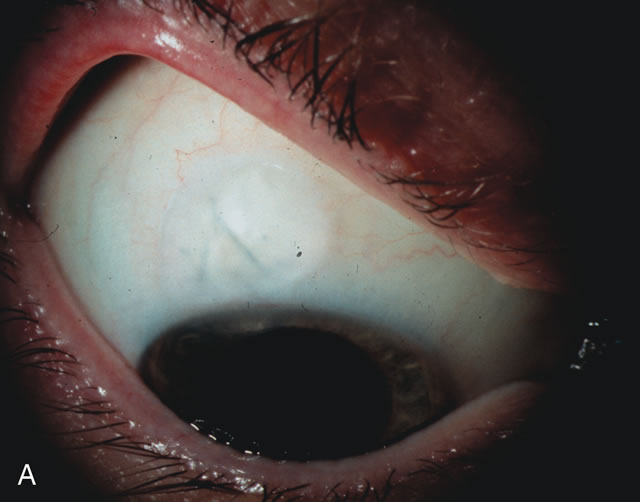

CATARACT EXTRACTION ALONE REDUCES IOP IN MOST EYES WITH ANGLE-CLOSURE GLAUCOMA

Uncomplicated cataract extraction substantially reduces IOP, along with the number of postoperative glaucoma medications in eyes with angle-closure glaucoma.146,147 When preoperative gonioscopy reveals PAS, along with adjacent areas of appositional closure, lens extraction alone in select cases may be a reasonable alternative to filtration surgery.148,149 Phacomorphic angle-closure disease due to enlargement of the lens with progressive angle crowding is eliminated following lens extraction. The width and depth of the anterior chamber angle in eyes with angle-closure glaucoma increases significantly after cataract extraction with IOL implantation and becomes similar to open-angle glaucoma and normal eyes.150,151 (Fig. 5). Combining phacoemulsification, IOL implantation, and limited goniosynechialysis is effective in the treatment of cataract and chronic angle-closure glaucoma.152 Phacoemulsification with implantation of a foldable IOL is more effective in reducing IOP and improving visual acuity than surgical peripheral iridectomy in eyes with acute angle-closure glaucoma.153

Fig. 5. Anterior chamber angle changes associated with lens extraction and PCIOL This 65-year-old Vietnamese woman has a long-standing history of chronic angle-closure glaucoma treated with laser peripheral iridectomy. The optic nerve demonstrated mild glaucomatous damage and IOP was moderately controlled on two antiglaucoma medications. The cataract was removed through temporal clear corneal phacoemulsification with foldable acrylic IOL. A. Symptomatic cataract in narrow-angle glaucoma eye with patent iridectomy. B. Intraoperative goniophotograph showing crowding of angle with increasing narrowness due to phacomorphic component. C. Intraoperative photograph showing temporal clear corneal approach with IOL in the capsular bag. D. Intraoperative goniophotograph demonstrating deepening of chamber angle following lens extraction. Proposed theories for IOP reduction following lens extraction with complete wound closure:

1. Anterior chamber deepening with improved access to trabecular meshwork

2. Increase in traction on the trabecular meshwork

3. Improved outflow facility mediated by an increase in prostaglandin release

4. Reduction in aqueous humor production

5. Atrophy of ciliary body processes

6. Goniosynechialysis due to intraoperative over deepening of AC with viscoelastic

7. Relief of undiagnosed pupil block